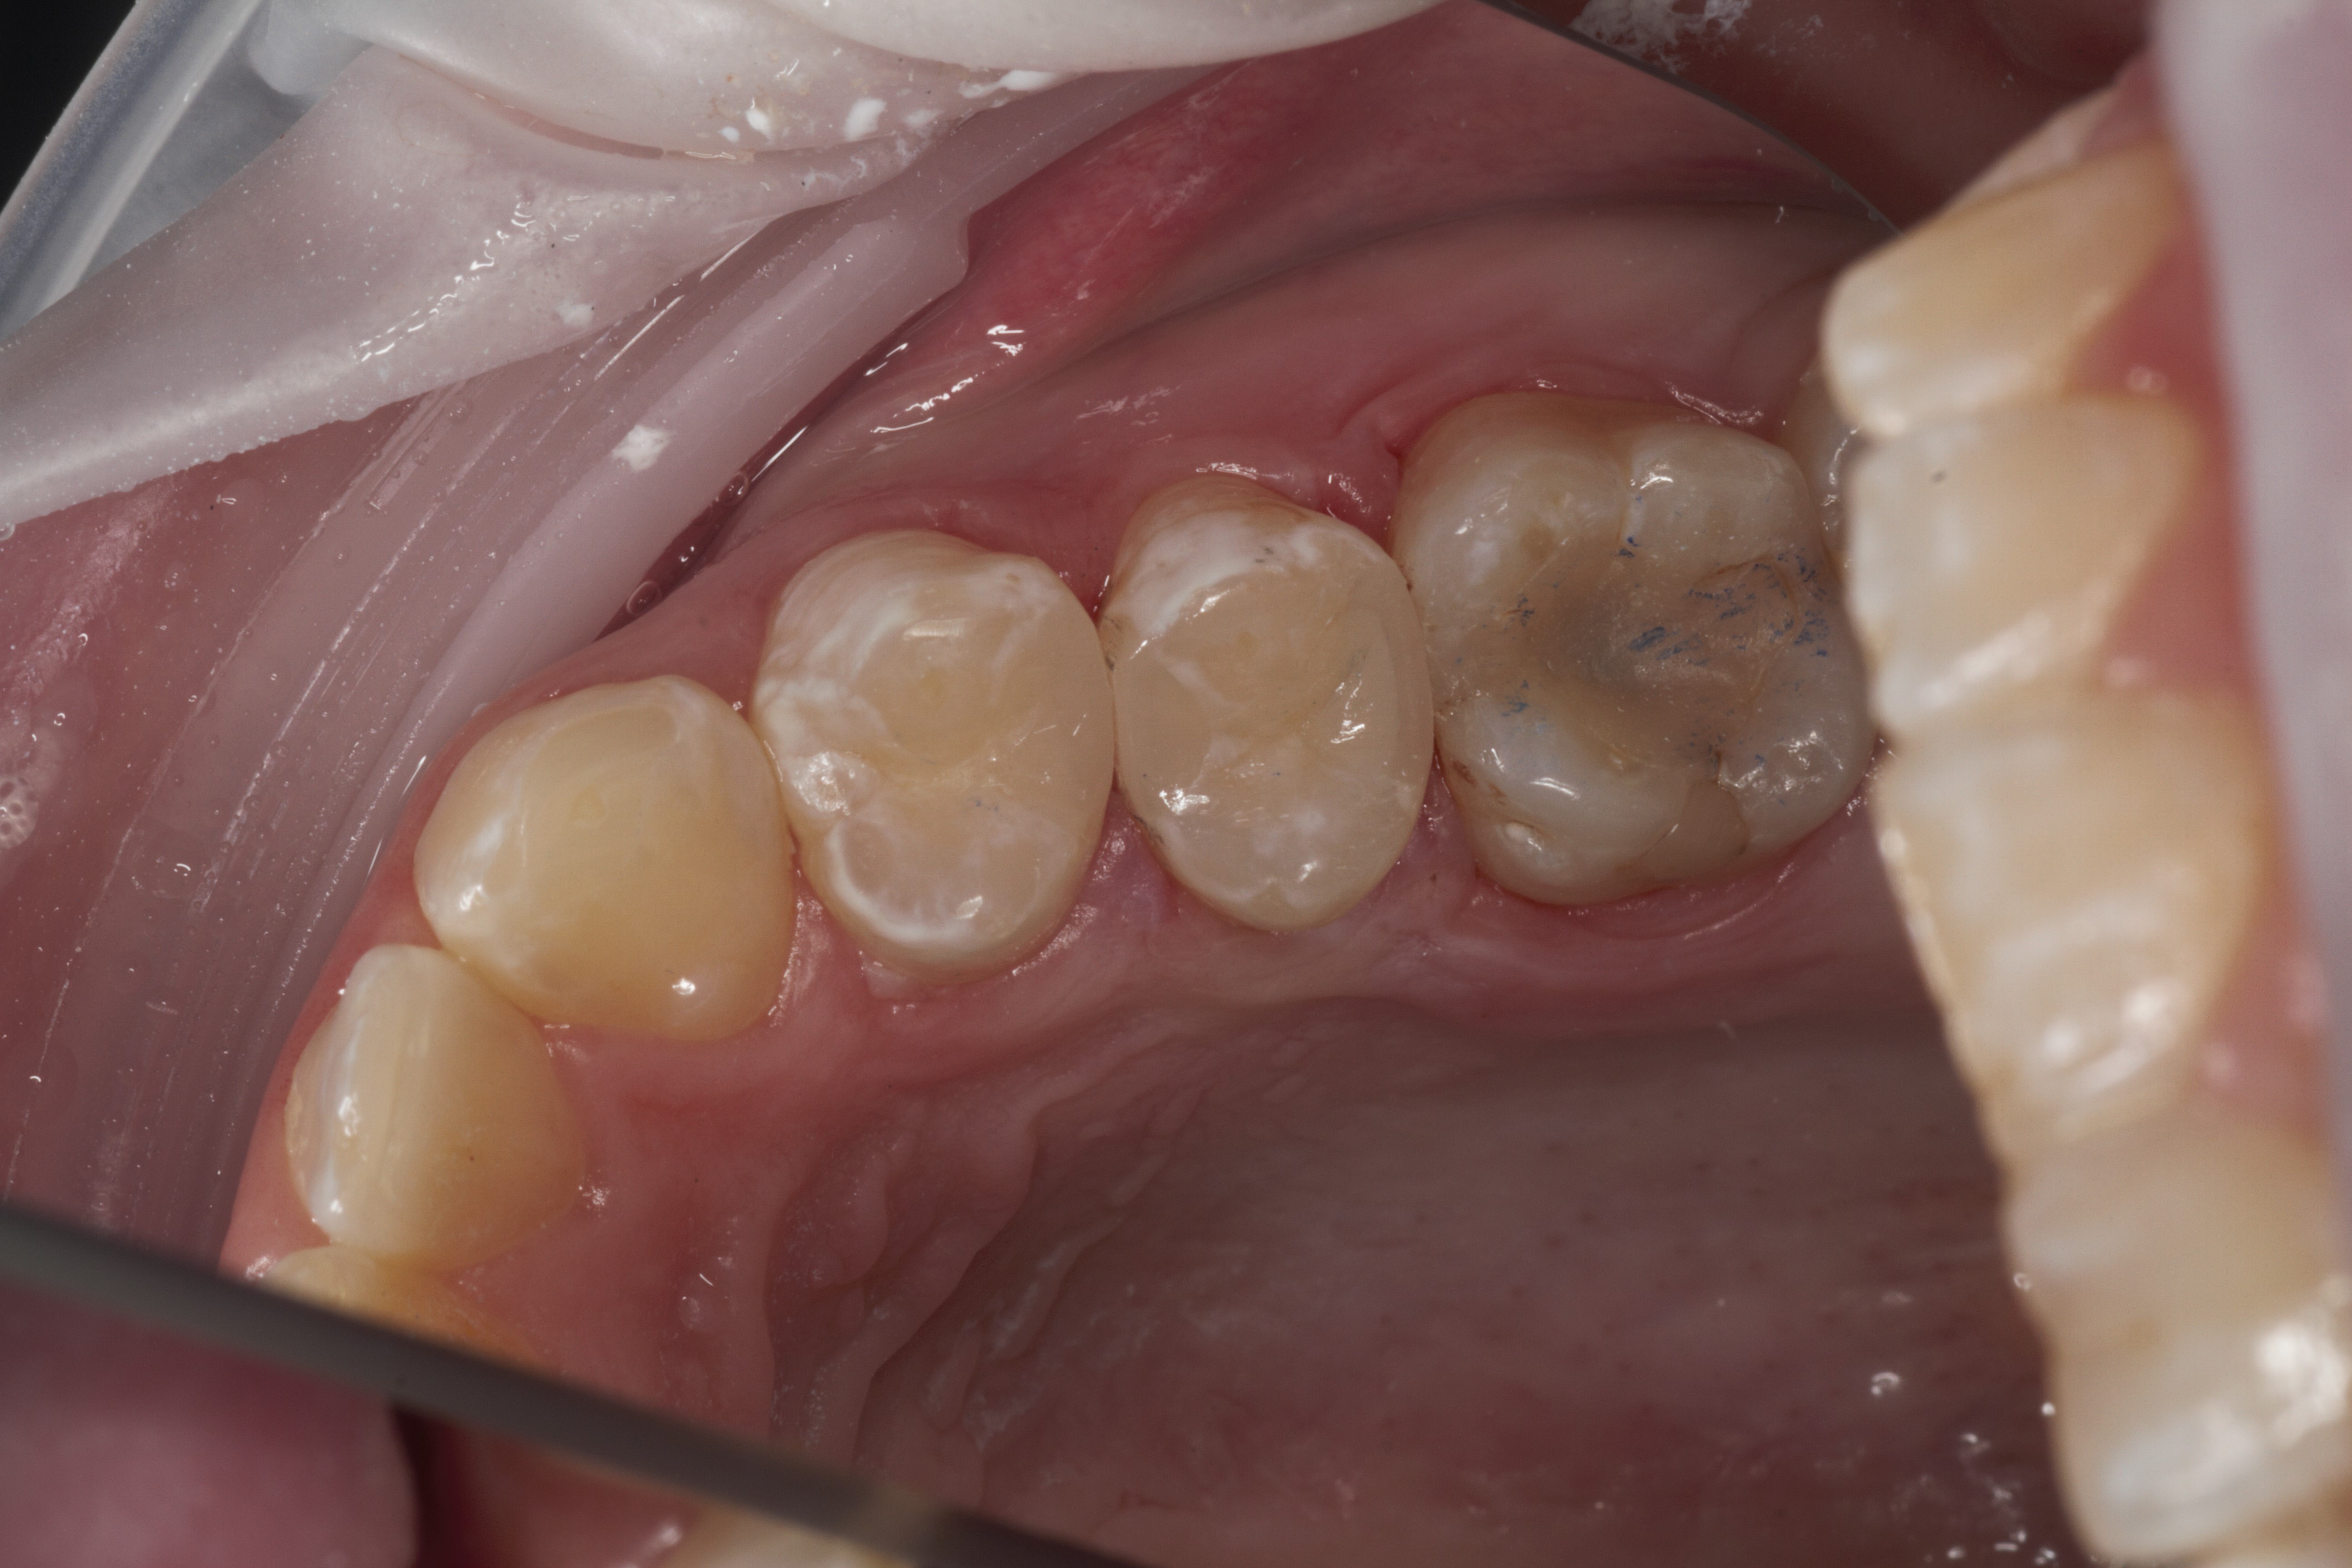

- Эстетическая реставрации жевательной и фронтальной группы зубов современными пломбировочными материалами, диагностика кариеса на ранних этапах развития, предупреждение образования вторичного кариеса в области запломбированных зубов